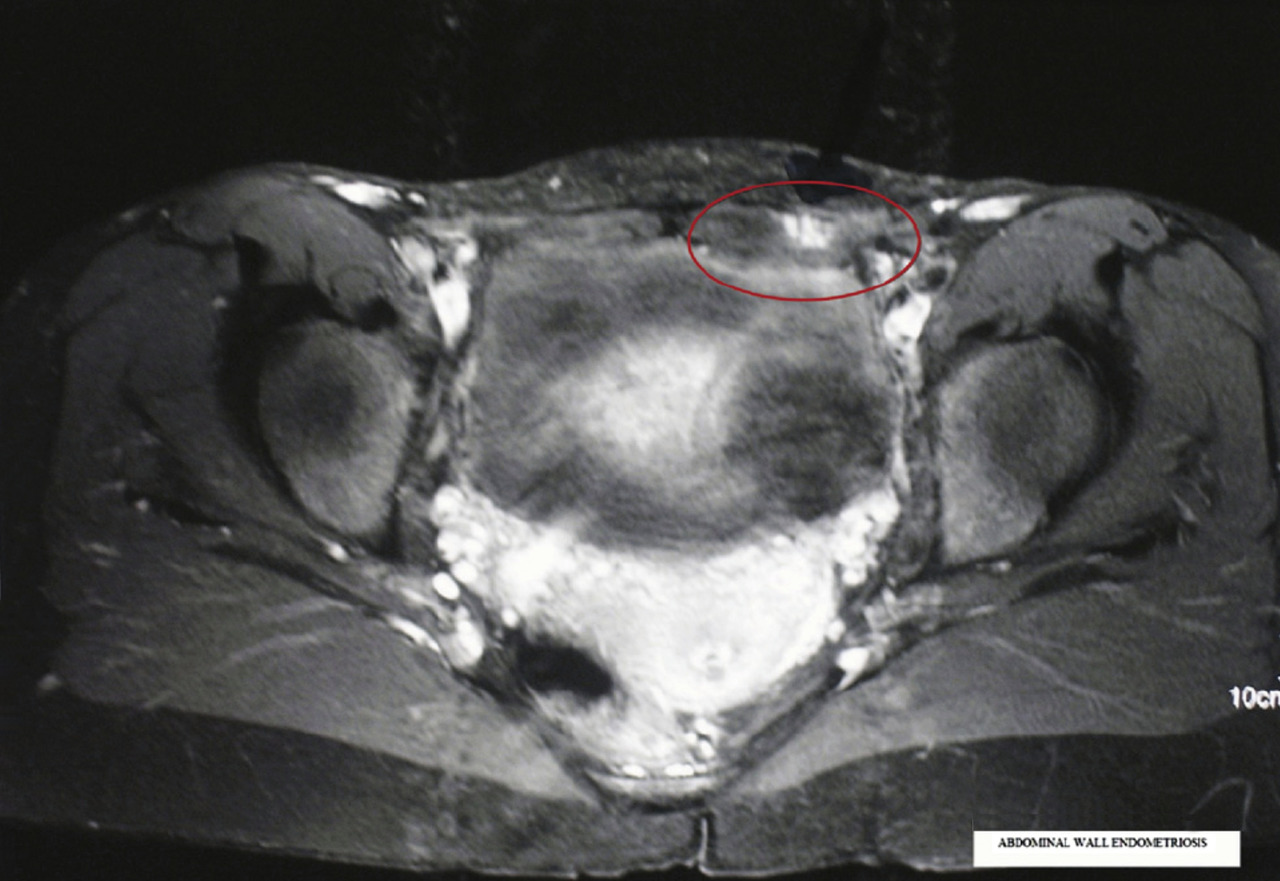

La tomodensitométrie n’est pas un bon examen pour diagnostiquer le nodule endométriosique pariétal dans la cicatrice de césarienne (fig 2).27 L’imagerie par résonance magnétique est plus adaptée pour l’exploration de la région pelvienne ; elle permet de rechercher une endométriose pelvienne dans le même temps qu’elle détermine les dimensions et la localisation précise du nodule endométriosique dans la paroi (fig. 3).30, 31